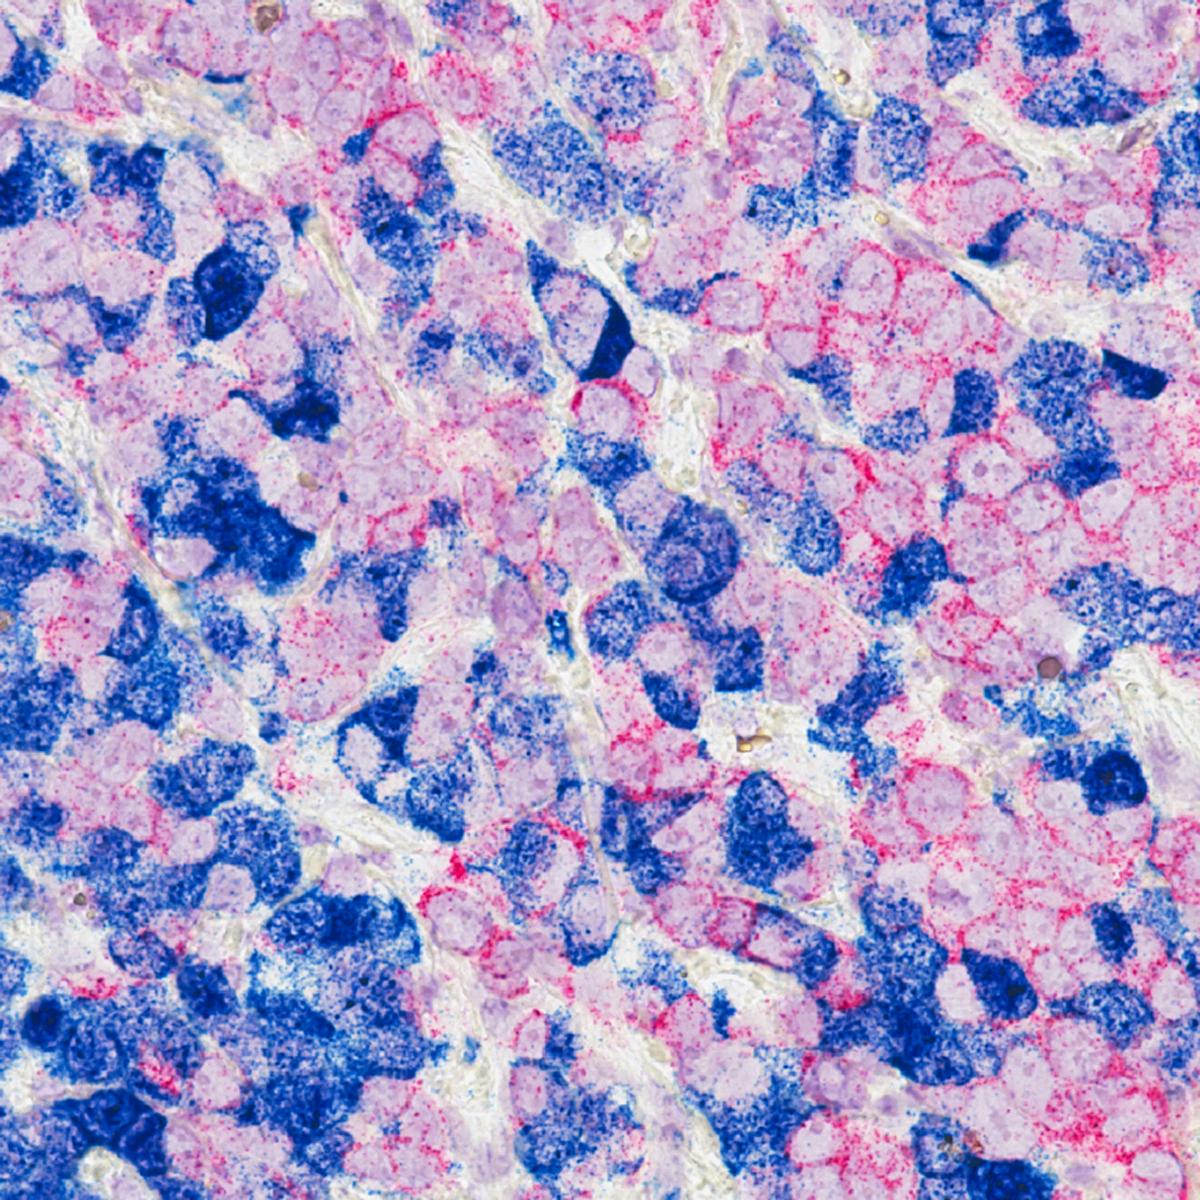

Sophia Lunt, an MSU professor in biochemistry and molecular biology in the College of Natural Science, and Richard Lunt, an MSU professor and Johansen-Crosby Endowed Professor in Chemical Engineering in the College of Engineering, along with Vincent Lavallo, a professor of chemistry at the University of California, Riverside, have combined their expertise to help develop new light-sensitive chemicals called cyanine-carborane salts that are used in photodynamic therapy, or PDT, to destroy metastatic breast cancer tumors in mice with minimal side effects.

During PDT, light-sensitive chemicals are circulated throughout the body where they collect inside cancer cells. Near-infrared light, which is invisible to the human eye, can penetrate deeper into the body and activate these salts which act like a “smart” bomb, killing cancer cells while sparing healthy cells.

These new cyanine-carborane salts offer an advantage over the chemicals traditionally used in PDT because they are absorbed by cancer cells and provide more effective treatment.